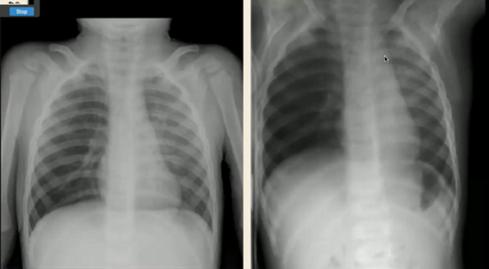

图10.支气管性肺炎(左)与间质性肺炎(右)以下是细菌性感染的一些典型胸片:

图11.肺实变、大片阴影、肺量增加

图12.肺实变、胸腔积液

图13.球型实变(不应诊断为肿瘤/异物)

图14.“脊柱征”:位于心影后的下叶肺炎在正位片中不易看出,侧位片中可表现为椎体变白正常侧位片(左)与下叶肺炎(右)

以下是病毒性感染的一些典型胸片:

图15.沿肺门分布的线条状阴影,不累及胸膜边界

图16.正位片(左):肺不张(右上肺野肺裂上移);侧位片(右):过度充气(横隔变平)③支原体肺炎:可兼有细菌性及病毒性肺炎的表现,弥漫片状阴影或间质线性阴影,最常见表现为双下肺阴影伴积液,常伴有肺门淋巴结肿大。